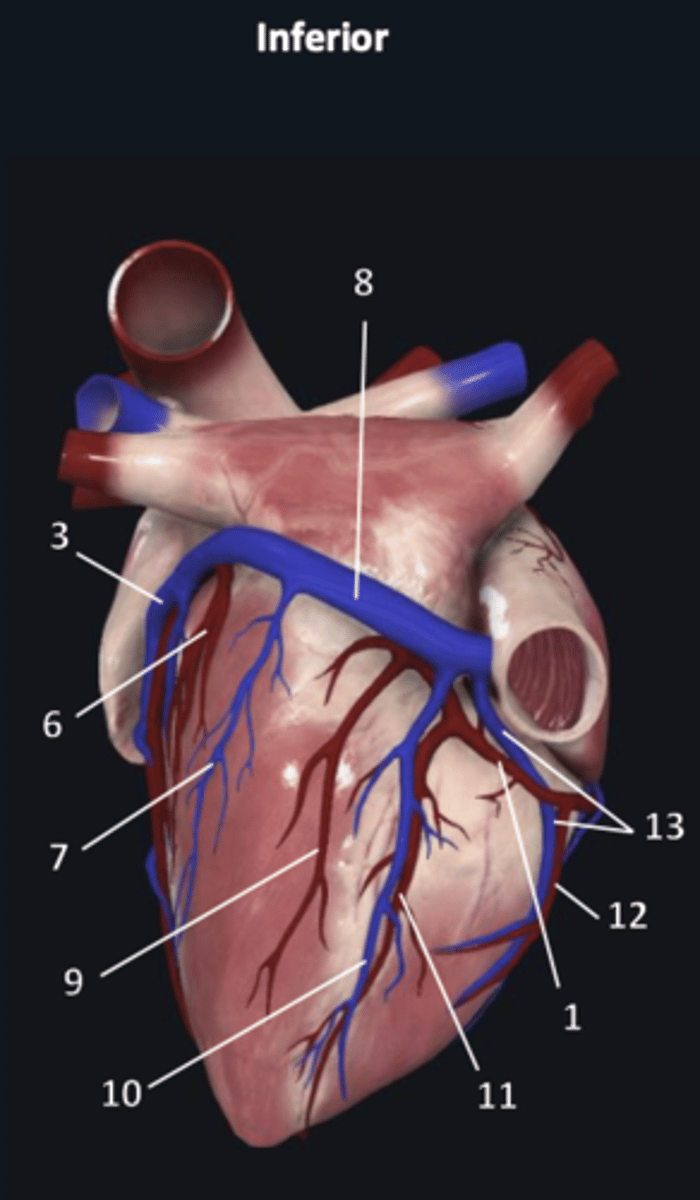

right coronary artery

1 (red)

great cardiac vein

3

posterior left ventricular artery

6

posterior vein of left ventricle

7

coronary sinus

8

right posterolateral artery

9

middle cardiac vein

10

posterior interventricular artery

11

right marginal artery

12

small cardiac vein

13